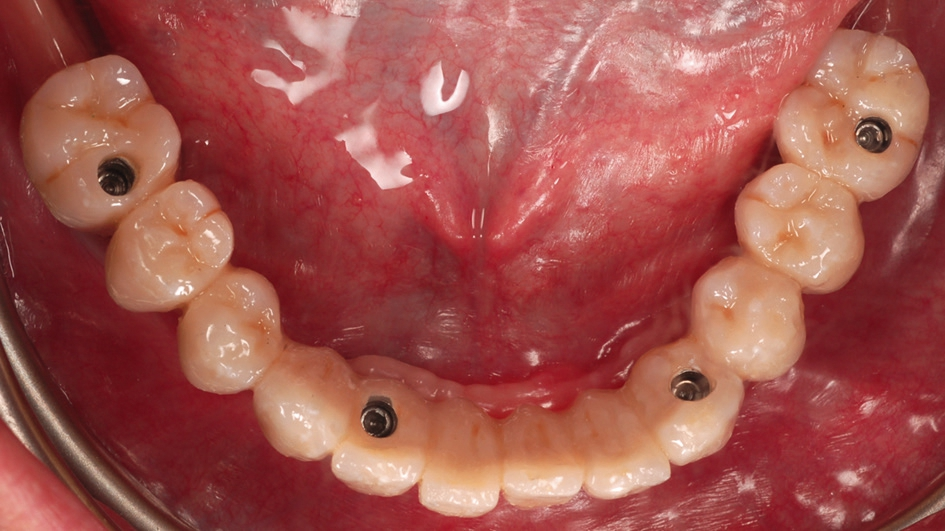

Die Implantatinsertion wurde unter Lokalanästhesie und unter direkter Sicht mit Bildung eines Mukoperiostlappens durchgeführt. Das offene Vorgehen wurde gewählt, da eine fortgeschrittene Resorption des knöchernen Alveolarfortsatzes in oro-vestibulärer Richtung vorlag und auf diese Weise eine sehr gute Beurteilung der Knochenkonturen und der Qualität des Knochens sowie eine Implantatpositionierung unter direkter Sicht ermöglicht wurden [33-35]. Es wurden BEGO Semados® RSX Implantate (BEGO Implant Systems) mit den Standarddurchmessern 3,75 mm (regio 036 und 043) und 4,10 mm (regio 046 und 033) verwendet. Die Implantation erfolgte freihändig nach dem Standardprotokoll des Herstellers. Alle Implantate wurden, mit Ausnahme des Implantats in regio 043, epikrestal am bukkalen Aspekt eingesetzt (Abb. 4). Da der Alveolarkamm sattelförmig gestaltet war, lag der Implantathals bei allen Implantaten approximal jeweils etwa 1,0 mm subkrestal. Das Implantat in regio 043 wurde nach lingual hin ca. 2,0 mm subkrestal inseriert.

Aufgrund des guten vertikalen Knochenangebotes konnten im Eckzahnbereich 11,5 mm lange Implantate und im Seitenzahnbereich Implantate mit der Länge von 10 mm verwendet werden. Dabei war eine Abwinkelung der Implantate im Seitenzahnbereich – wie sonst bei der klassischen All-on-4® Methode üblich – nicht notwendig (Abb. 5).

Nach einer weiteren siebenwöchigen Einheilungszeit wurden die Implantate freigelegt und mit Gingivaformern mit Platform Switch Ausführung (PS HP, BEGO Implant Systems) versorgt (Abb. 7).